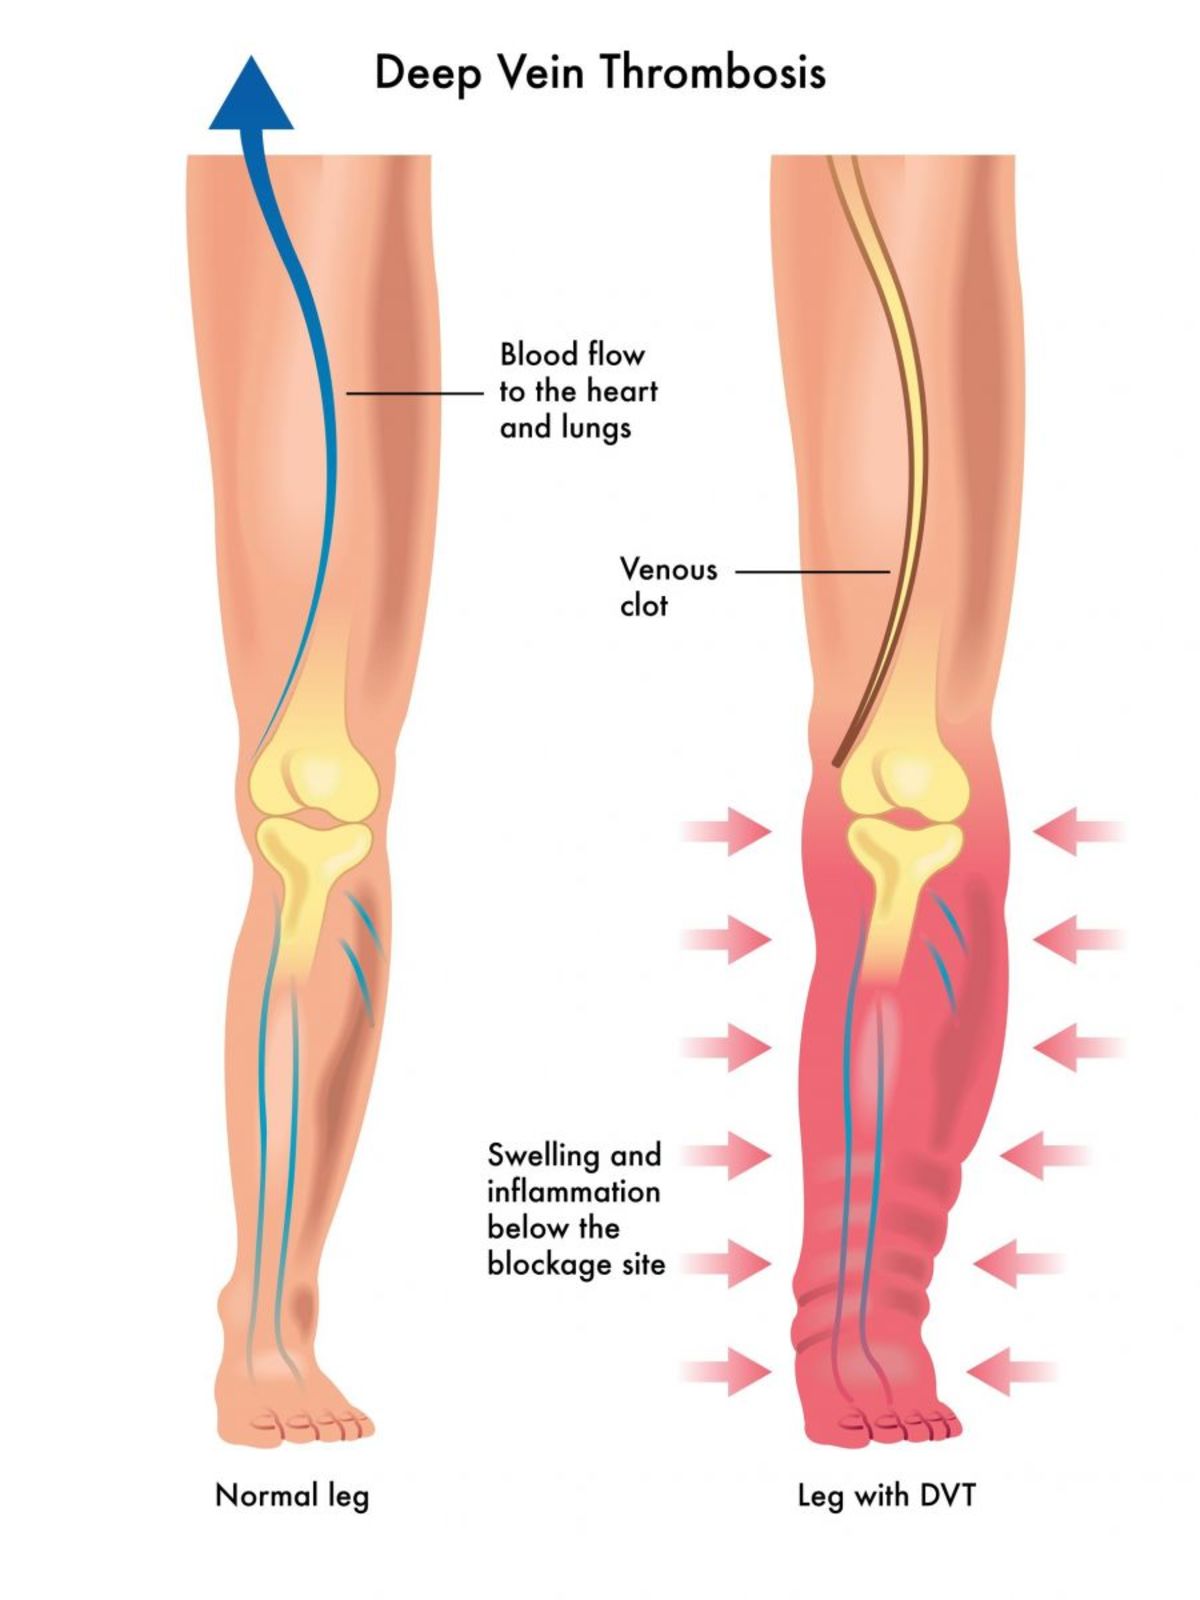

Φλεβική θρόμβωση οι ειδικοί την αποκαλούν και σιωπηλό δολοφόνο. Ποιοι κινδυνεύουν και τι πραγματικά συμβαίνει; Η φλεβική θρόμβωση συμβαίνει όταν ένας θρόμβος αίματος σχηματίζει σε μία ή περισσότερες από τις εν τω βάθει φλέβες του σώματός σας, συνήθως στα πόδια σας. Μπορεί να προκαλέσει πόνο στα κάτω άκρα ή πρήξιμο, αλλά μπορεί να εξελιχθεί και χωρίς συμπτώματα.

Η εν τω βάθει φλεβική θρόμβωση μπορεί να αναπτυχθεί αν έχετε ορισμένες ιατρικές παθήσεις που επηρεάζουν τον τρόπο με τον οποίο πήζει το αίμα σας. Μπορεί επίσης να σας συμβεί από παρατεταμένη ακινησία, όπως μετά από κάποια χειρουργική επέμβαση. Μετά από ένα ατύχημα, ή όταν είστε καθηλωμένοι σε ένα κρεβάτι για αρκετό καιρό.

Η φλεβική θρόμβωση είναι μια σοβαρή κατάσταση. Θρόμβοι αίματος στις φλέβες σας μπορεί να αποσπαστούν από το σημείο που σχηματίστηκαν. Να “ταξιδέψουν” στο κυκλοφορικό σας σύστημα και να φτάσουν στους πνεύμονές σας. Εμποδίζοντας τη ροή του αίματος προς αυτούς (πνευμονική εμβολή).

Πρήξιμο στο ένα πόδι. Σπάνια, μπορεί να υπάρχει πρήξιμο και στα δύο πόδια.

Πόνος στο πόδι. Ο πόνος συχνά ξεκινά στην κνήμη και θα τον αισθανθείτε σαν να είναι κράμπα ή γενικευμένος πόνος.

Υπάρχει, ωστόσο, μεγάλη πιθανότητα η ΕΒΦΘ να συμβεί χωρίς εμφανή συμπτώματα.